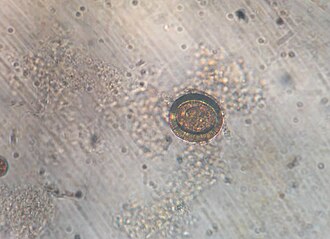

Datoteka:Taenia species egg.JPG

Jaje trakavice na preparatu stolice.